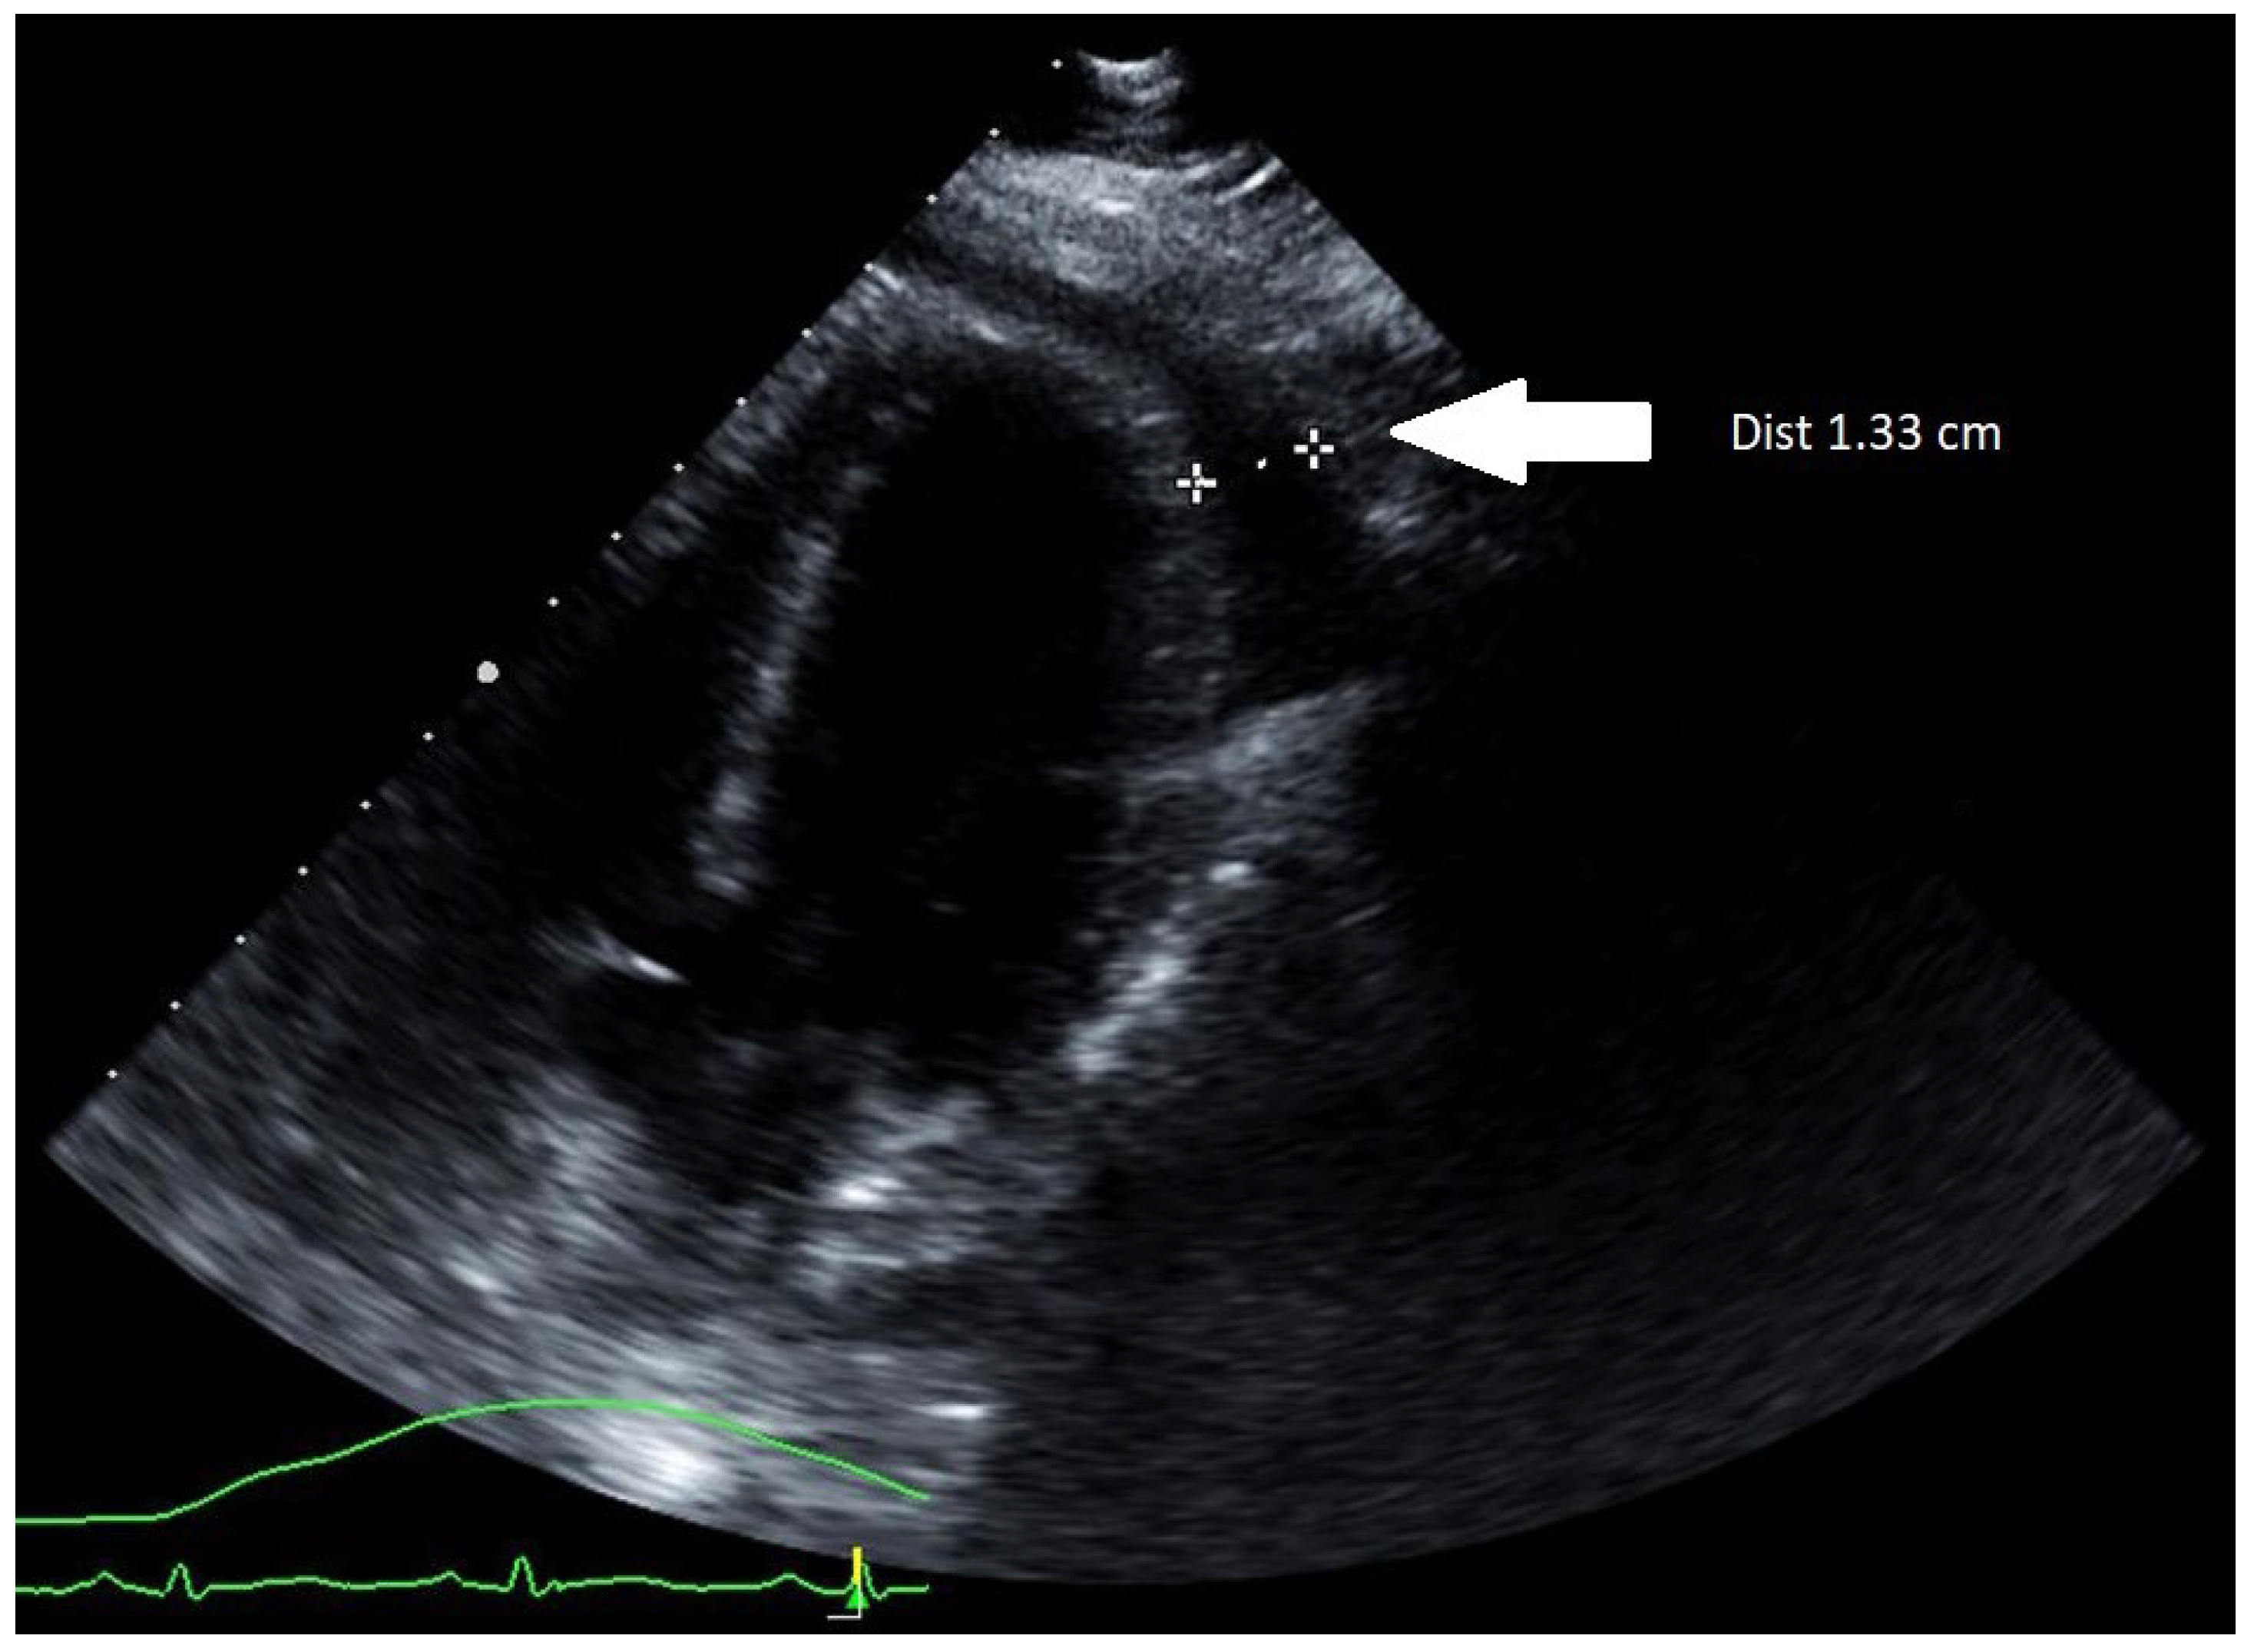

The patient was intubated, and an emergent subxiphoid pericardial window was performed with drainage of 250 milliliters of clear pericardial fluid. The patient’s hemodynamic parameters immediately improved, but not long after the patient became hypotensive and required a large volume of IV fluids totaling 14 L of crystalloid saline. Norepinephrine infusion was also initiated at the rate of 0.1 micrograms/kilograms/minute. The patient’s troponins continued to increase with repeat TTE, demonstrating decreased left ventricular (LV) systolic function to 44% along with moderately increased concentric LV wall thickness (Figure 2A). Despite receiving significant amounts of crystalloid fluid and continuous norepinephrine of 0.15 micrograms/kilograms/minute, she remained in refractory shock, at which time epinephrine was added at the rate of 0.07 micrograms/kilograms/minute.

Figure 2. Parasternal short-axis view of TTE: (A) during the acute illness revealing 15 mm LV wall thickness; (B) 1-month follow-up demonstrating 10 mm LV wall thickness.

Her hospital course was complicated by rhabdomyolysis, acute kidney injury, and intensive care unit-acquired weakness requiring intensive physical therapy. After 20 days of hospitalization, she was discharged to a rehabilitation facility. Her discharge medication regimen consisted of colchicine 0.6 milligrams daily for an anticipated 3-month course and oral furosemide 40 milligrams daily. After one month, a follow-up TTE demonstrated recovered systolic function with LV ejection fraction of 62%, resolution of myocardial edema, and no evidence of recurrent pericardial effusion (Figure 2B). No long-term complications were encountered on a subsequent follow-up.